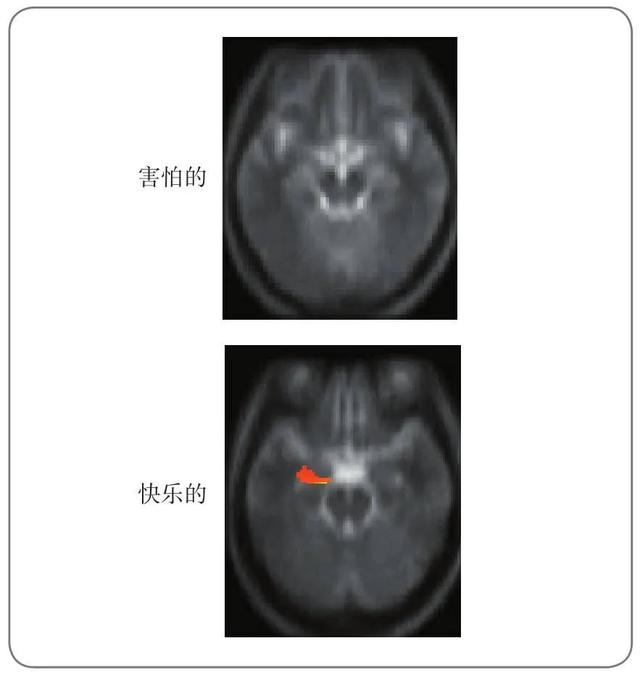

☞研究者证明,与五因素模型中的特征差异相对应,个体的脑功能是有差异的。

图13.4 外倾性对左侧杏仁核功能的影响

8种人格类型,人格类型测试mbti免费(人格的类型)

参与者观看害怕的和快乐的面孔。图中的红色区域表明,外倾性和杏仁核的活动正相关。对于害怕的面孔,却没有发现这种相关。然而对于快乐的面孔,外倾性高的个体其左侧杏仁核有大量激活。